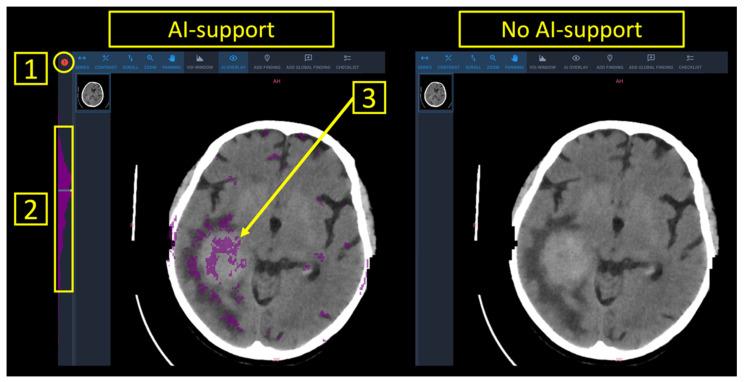

Most artificial intelligence (AI) systems are restricted to solving a pre-defined task, thus limiting their generalizability to unselected datasets. Anomaly detection relieves this shortfall by flagging all pathologies as deviations from a learned norm. Here, we investigate whether diagnostic accuracy and reporting times can be improved by an anomaly detection tool for head computed tomography (CT), tailored to provide patient-level triage and voxel-based highlighting of pathologies.

大多数人工智能(AI)系统仅限于解决预定义任务,因此限制了它们对未选定数据集的通用性。异常检测通过将所有病变标记为与学习到的规范的偏差来弥补这一不足。在此,我们研究一种针对头部计算机断层扫描(CT)的异常检测工具能否提高诊断准确性和报告时间,该工具旨在提供患者级别的分诊和基于体素的病变突出显示。